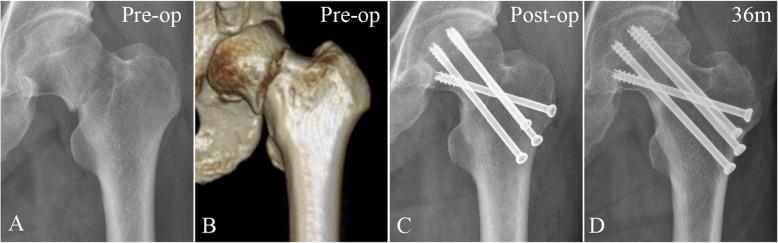

The optimal internal fixation strategy for vertical femoral neck fractures (VFNFs) in nongeriatric patients remains uncertain. Therefore, the purpose of this study was to compare the clinical prognoses and underlying mechanical characteristics of a novel off-axis screw technique with dynamic hip screws (DHSs) and three traditional parallel screws.

This study included a clinical investigation and a patient-specific finite element analysis (FEA). In the clinical investigation, VFNF patients were grouped by fixation type: (1) use of three parallel screws (G-TRI); (2) augmentation with an off-axis screw (G-ALP); and (3) DHS with an anti-rotational screw (G-DHS). Fixation failures (nonunion, femoral neck shortening (FNS), varus deformation, screw cut-out) and avascular necrosis (AVN) consequent to the three types of fixations were compared. In the FEA, twenty-four fixation models with the three fixation types were created based on the data of eight healthy volunteers. Models were assessed under walking conditions. Stiffness, interfragmentary motion (IFM), and implant stress were evaluated.

In the clinical investigation, the fixation failure rate was significantly (p < 0.05) lower in G-ALP (18.5%) than in G-DHS (37.5%) and G-TRI (39.3%). No significant difference in AVN was observed among the three fixation groups. In the FEA, stiffness and implant stress in the G-DHS models were significantly (p < 0.05) higher, and the IFM of G-ALP was significantly (p < 0.05) lower among the groups.

Among fixation types for VFNFs, the off-axis screw technique exhibited better interfragmentary stability (lowest IFM) and a lower fixation failure rate (especially FNS). Analyzing interfragmentary stability in biomechanical experiments is more consistent with clinical prognosis than construct stability for VFNFs, suggesting that internal fixations should aim for this outcome.